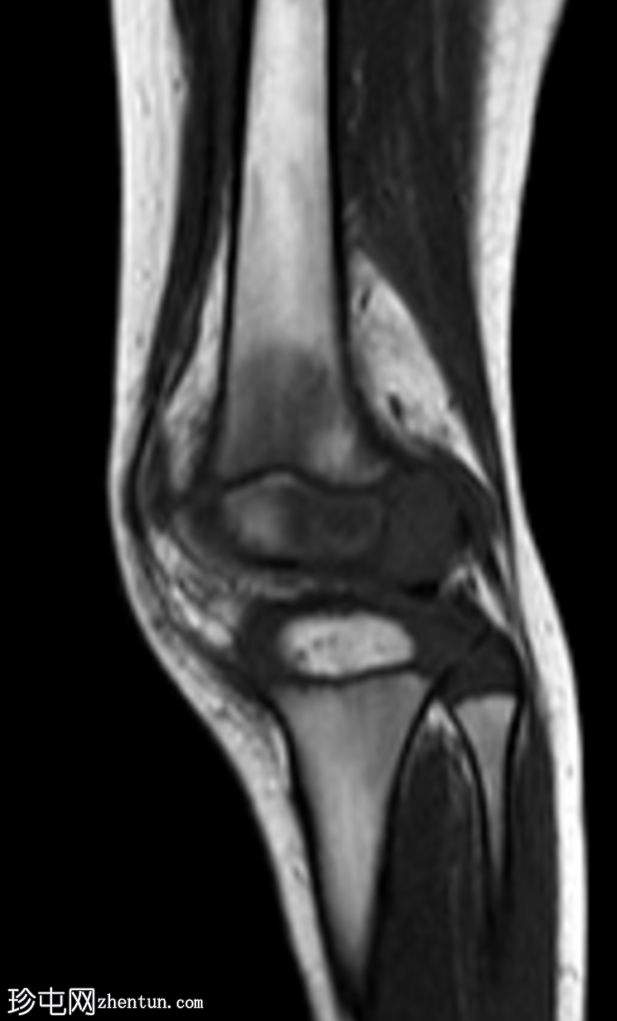

2.png

矢状位

T2加权像

右膝专用MRI显示股骨外侧髁后方髓内有一边界清晰的病灶,大小为1.6 x 0.9 cm,中心T1呈低信号,T2/STIR呈高信号,周围可见薄层T1高信号环(半影征)。

周围骨髓水肿广泛,在STIR序列上呈高信号,在T1加权像上呈低信号。